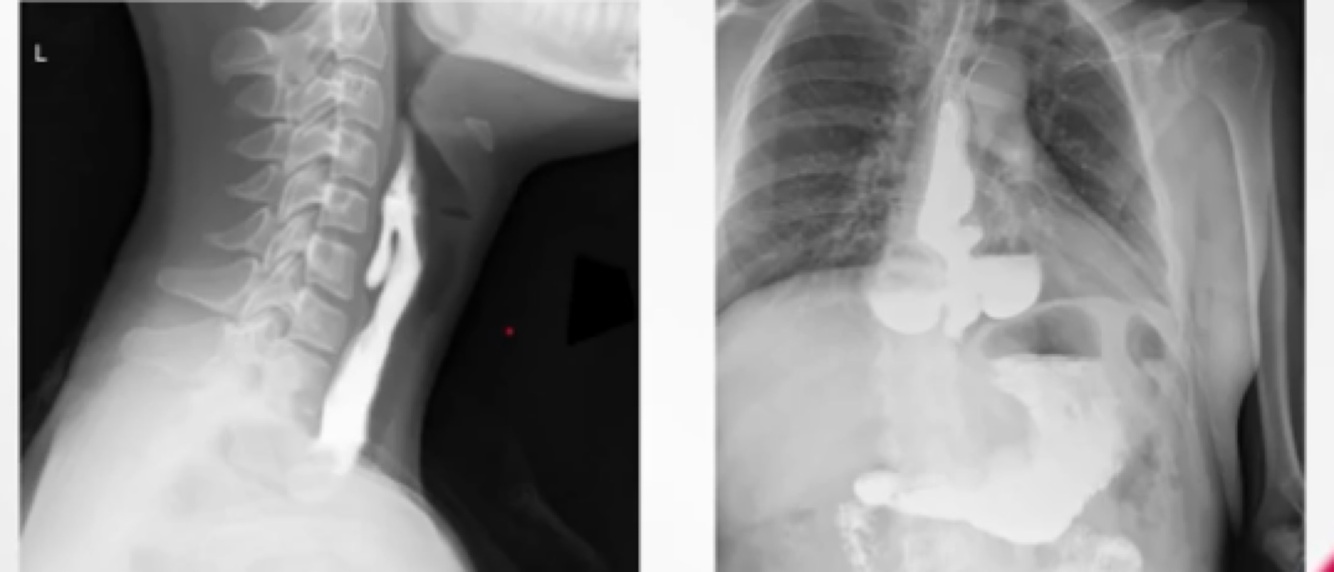

Quais os diagnósticos a seguir e quais os tipos de divertículos de esôfago?

Estes diverticulos estão no grupo dos…..

A

Divertículos de pulsão.